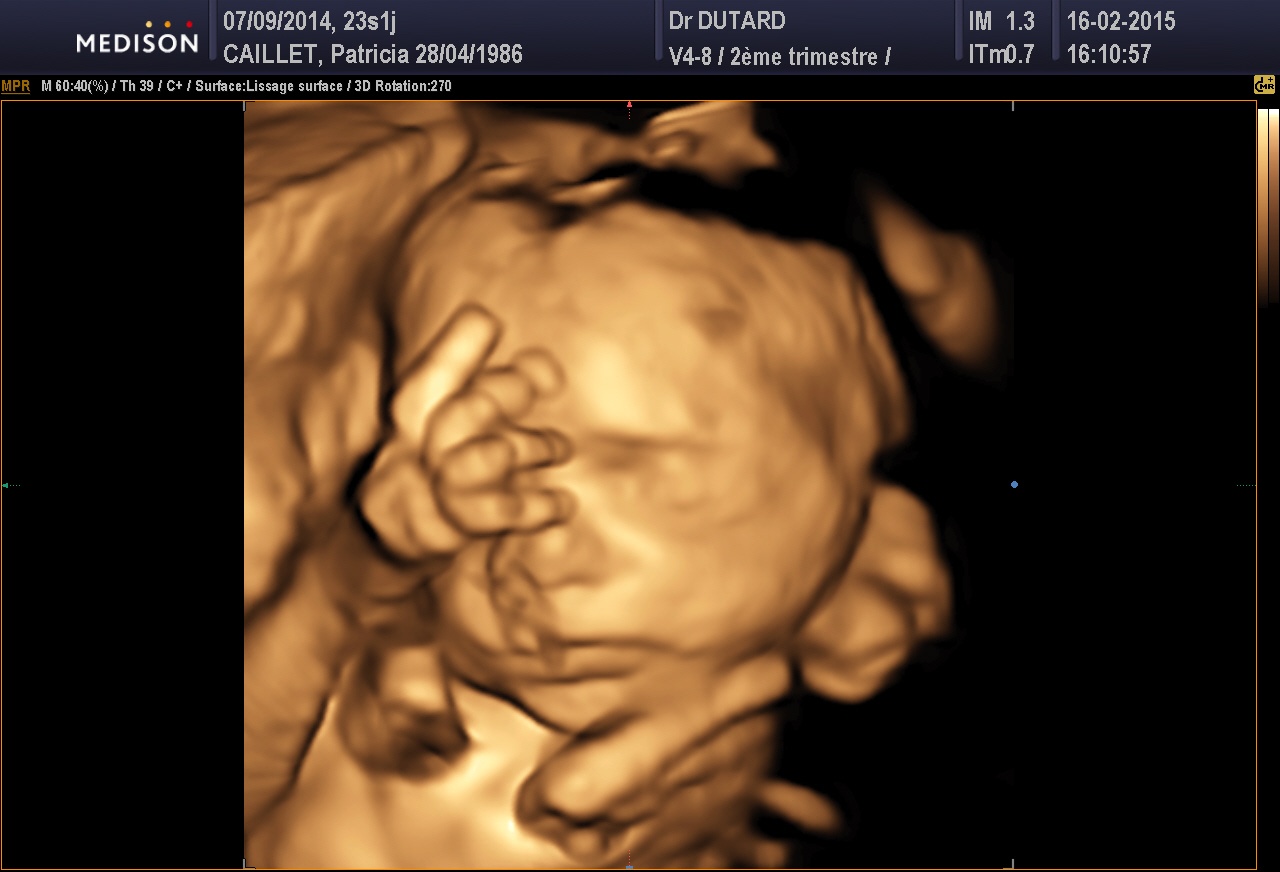

de son ptit bonhomme,puis on s en lasse pas de regarder ses echo surtout en 3d c est le top